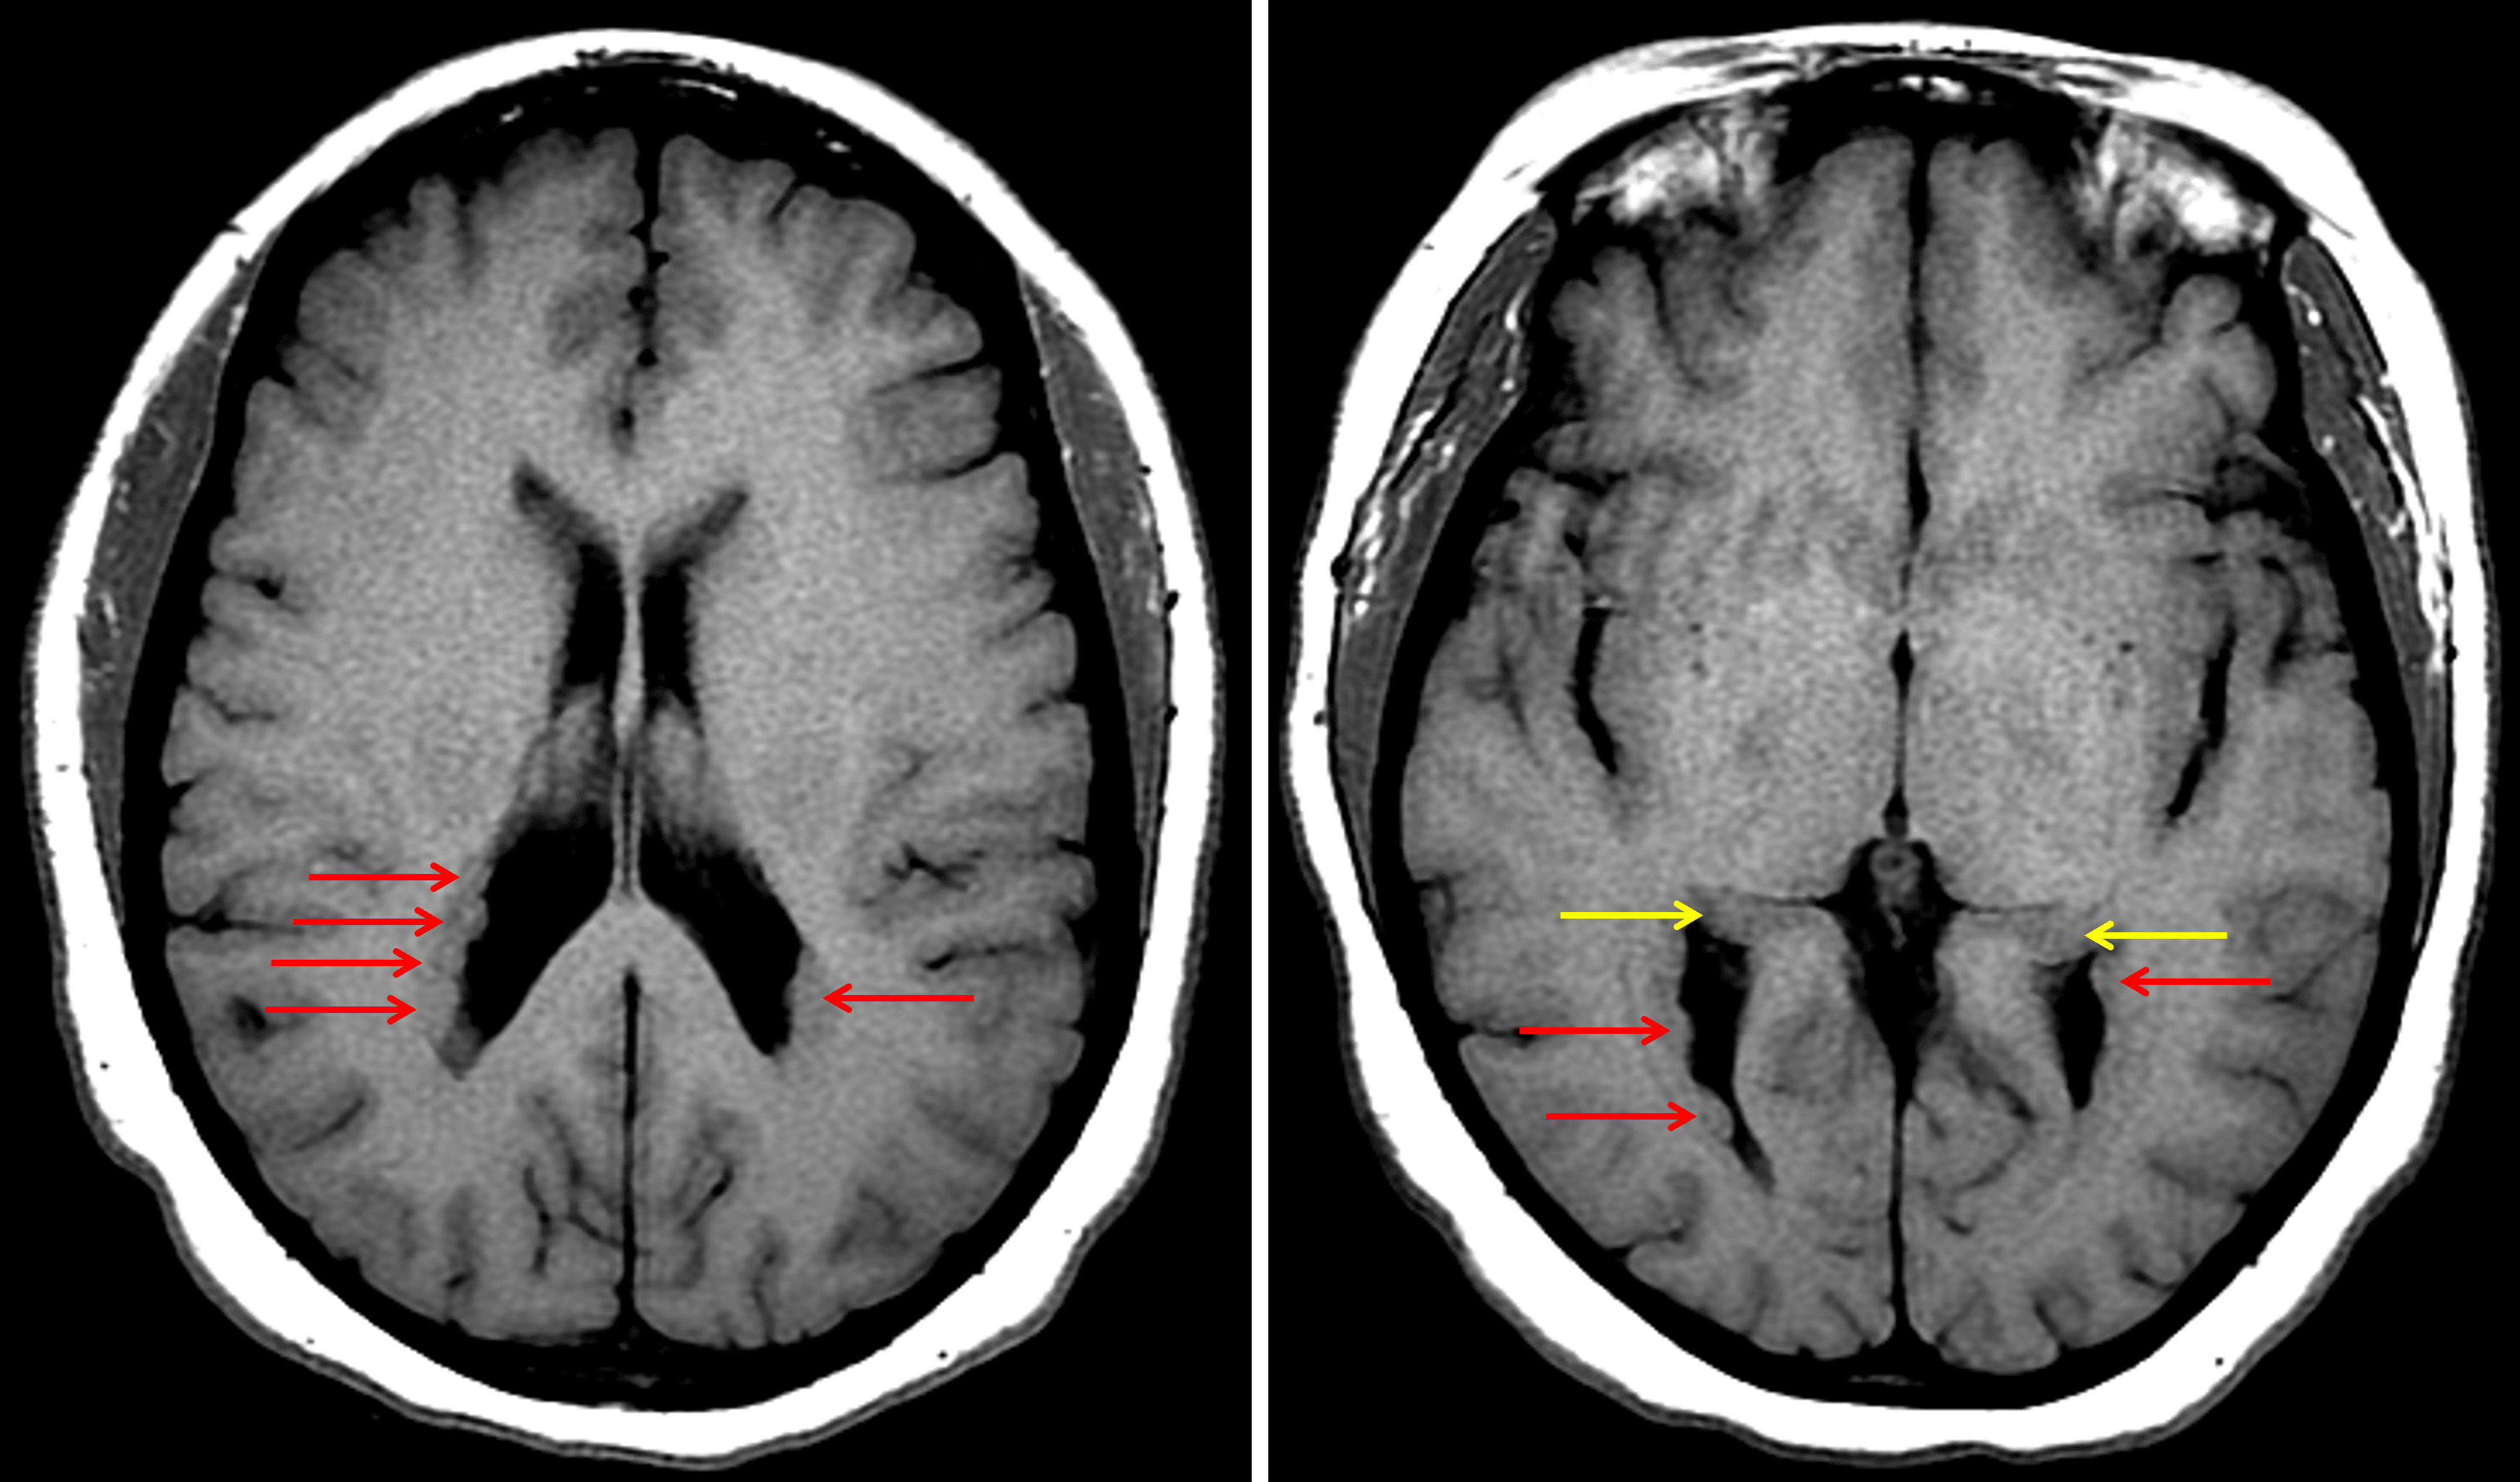

Multifocal nodular subependymal gray matter heterotopia (red arrows). Make sure not to mistake the caudate tails (yellow arrows) for gray matter heterotopia.

• Nodularity along the ependymal surface of both lateral ventricles, which is similar in attenuation to gray matter

• Nodularity along the ependymal surface of both lateral ventricles, which follows gray matter signal on all sequences

• No corresponding enhancement or susceptibility artifact

• No substantial intracranial mass effect or evidence of hydrocephalus

Gray matter heterotopia